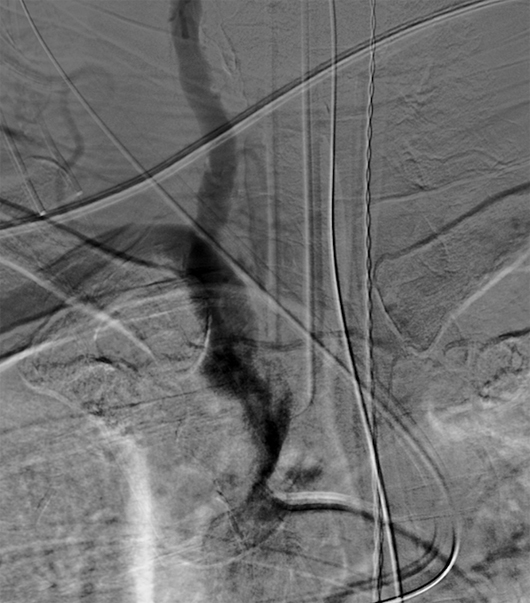

Cross-sectional CT imaging revealed severe atherosclerotic changes along the right innominate artery (Figures 1 and 2). A conventional diagnostic angiogram was then performed for further characterization of the stenosis and possible treatment. The left vertebral artery was the first vessel to be catheterized (Figure 3), and cervical angiography was performed. Retrograde contrast opacification of the contralateral right vertebral artery (Figure 4) and eventual contrast opacification of the right subclavian artery and the internal mammary artery was observed (Figures 5 and 6) suggesting right subclavian steal syndrome (SSS). Diagnostic angiograph evaluation of the remainder of the vessels was carried out and, eventually, a severe right innominate artery stenosis was detected. This was subsequently treated with placement of a stent. A thoracic arch aortogram depicts the postinterventional changes after successful stent placement in the right innominate artery with normal antegrade flow through the right vertebral artery (Figure 7).

Figure 7